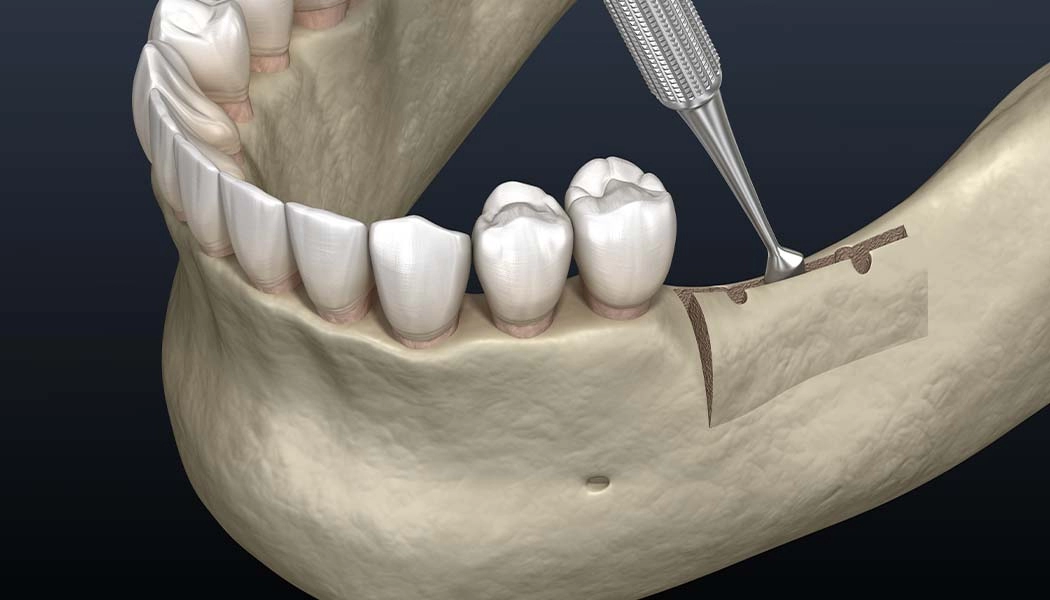

Расщепление альвеолярных отростков проводят путём механического расширения стенок гребня и заполнения образовавшейся полости костным материалом. За счет этого компенсируется нехватка ширины кости. Выполняется одномоментно с установкой имплантатов. После проведения имплантации и подсадки костной ткани десна ушивается. Метод применяется на нижней челюсти и на верхней для фронтальной зоны. При сильной вертикальной атрофии кости (нехватка высоты гребня) метод не применяется.